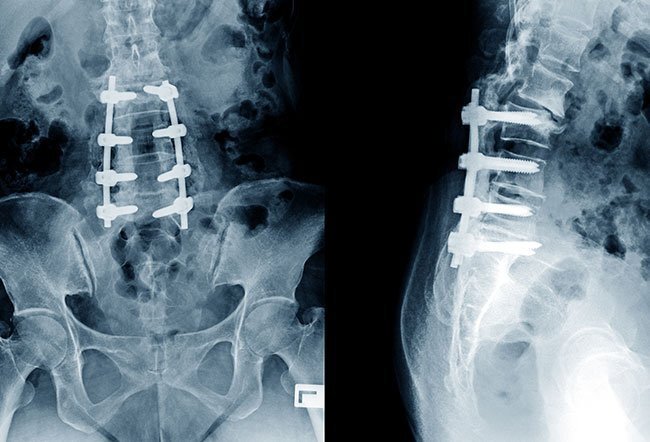

Spinal manipulation is based on movement and movement is healing. A chiropractor is uniquely positioned to leverage spinal manipulation to get our patients back to normal faster and more effectively. Especially when combined with exercises that are specific to the patient's injury. Exercise this extremely important for this back condition. Back issue and disc problems have been shown to have a high recurrence rate meaning they like to come back again 1-2 years down the road. Even surgeries have been shown to need another surgery up to 50% of the time. Exercise is one of the best treatments that you the patient can do to keep this problem from returning. The exercises that we give are short easy don’t need much equipment and can be done anywhere. Consistency is the key continue doing them and you odds of have recurrence of pain are greatly reduced.